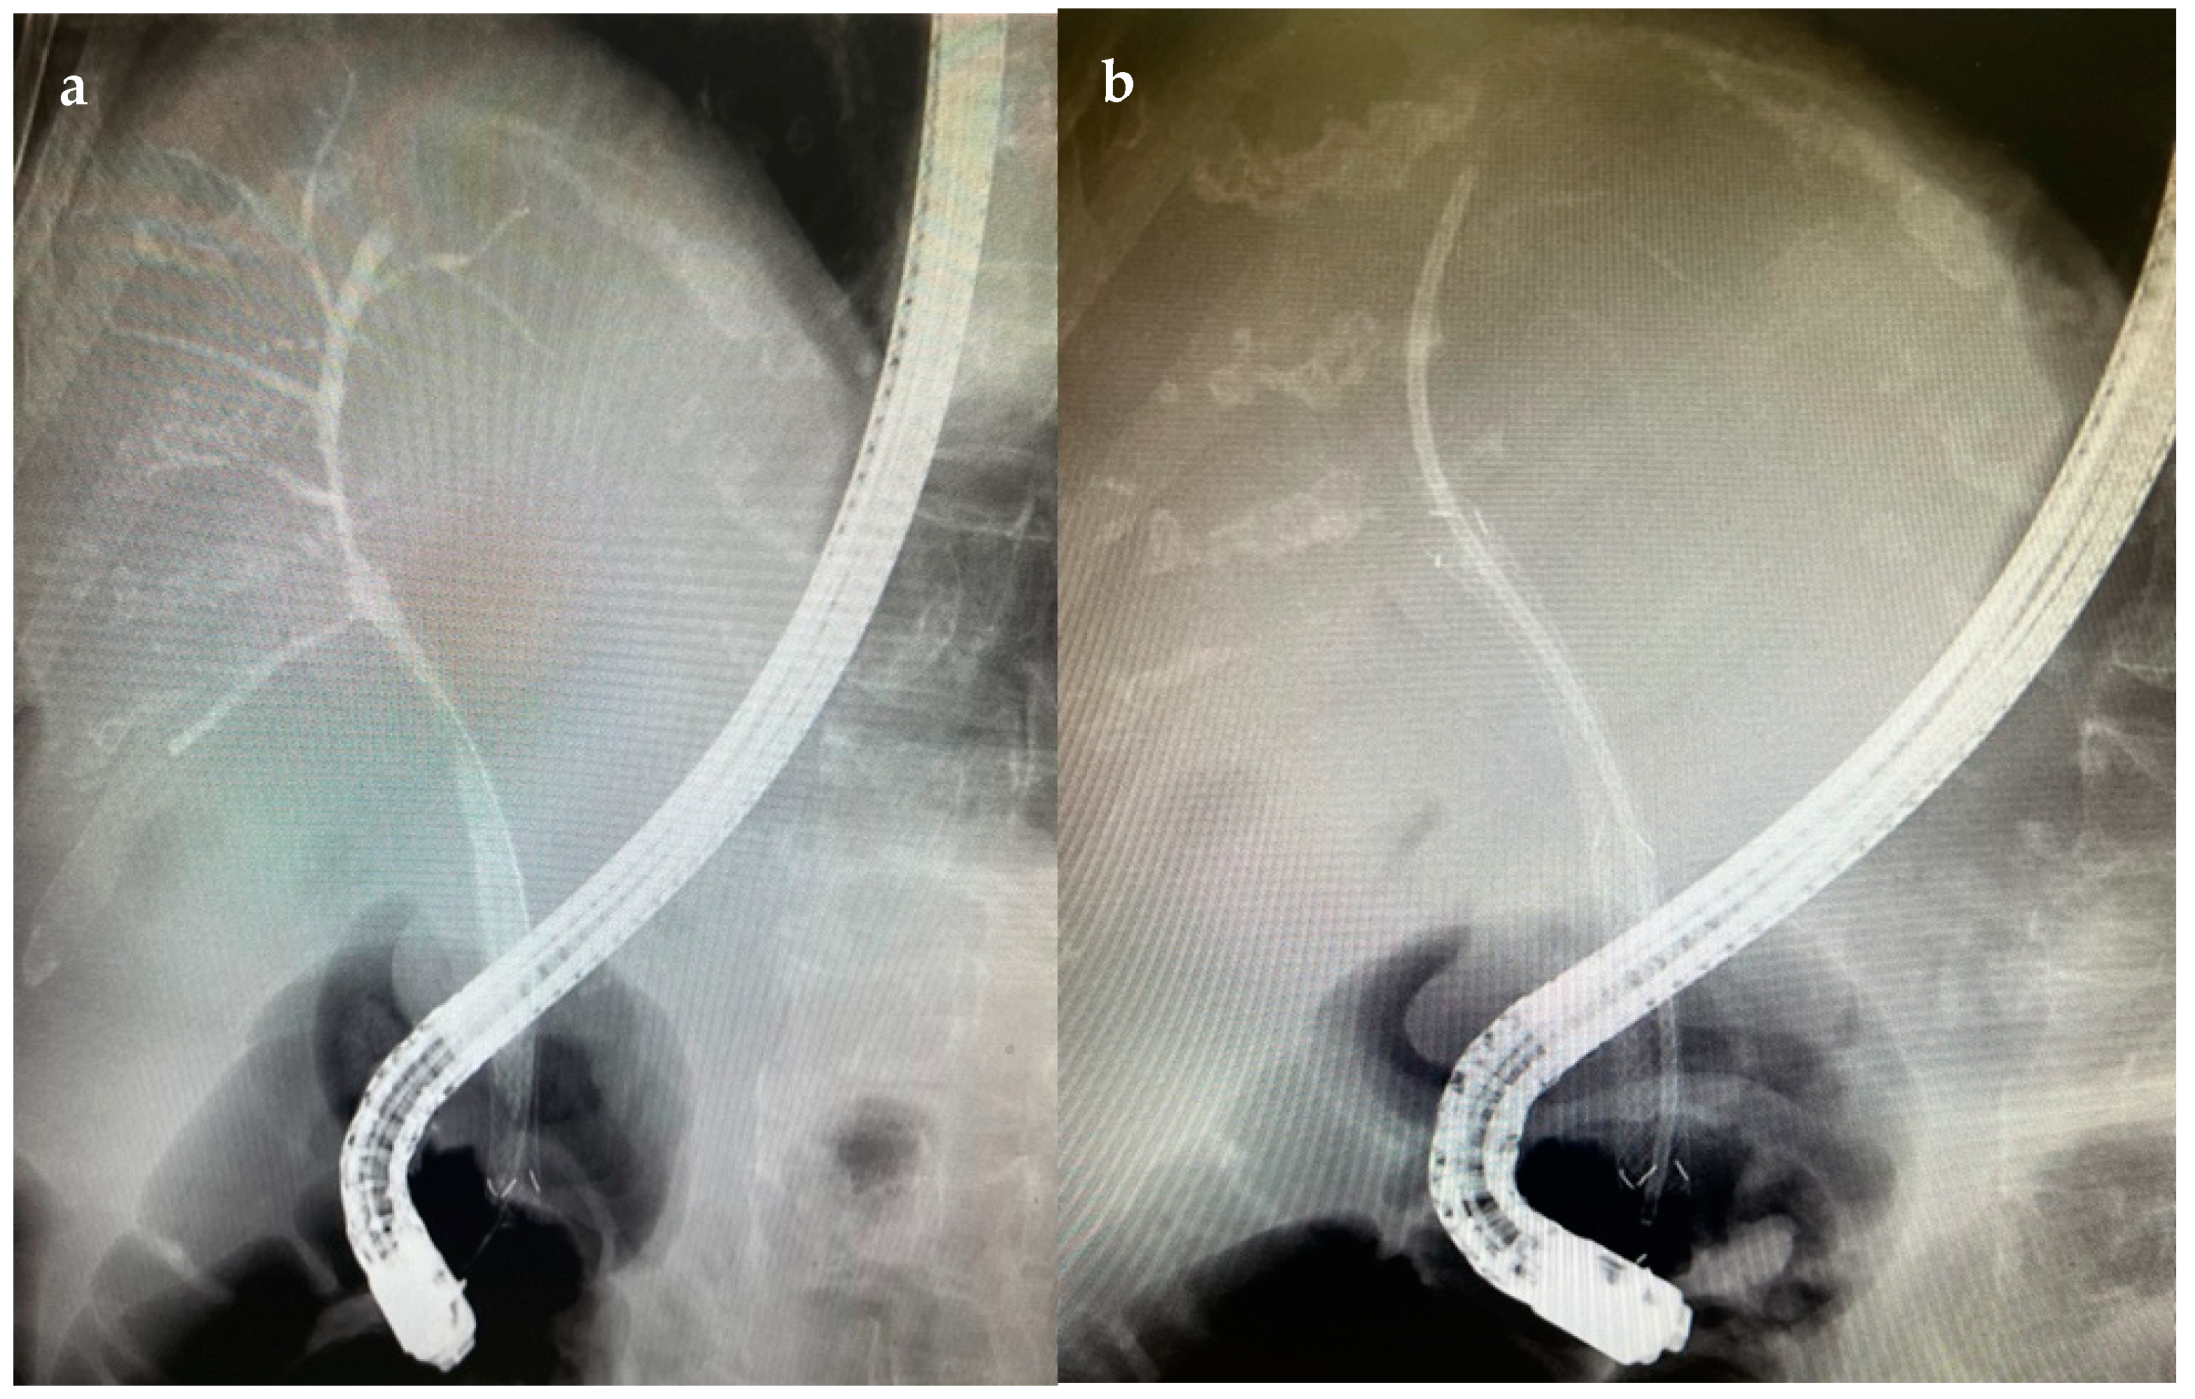

6.4.2. Endoscopic Retrograde Cholangiopancreatography (ERCP)

7.1.1. Endoscopic Biliary Stenting (EBS)

7.1.2. Endoscopic Nasobiliary Drainage (ENDB)